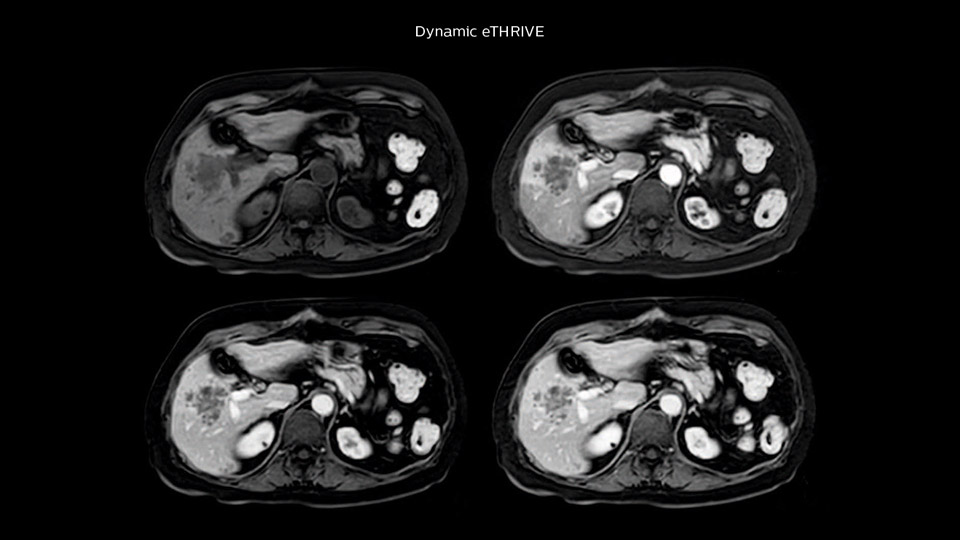

Comparison of liver MRI with and without MultiVane XD motion correction

In this example the image quality of the MultiVane XD images is evidently better than in the images without MultiVane XD. Ingenia 1.5T with dS Torso coil solution.

“We include mDIXON for the dynamic sequences because of the robust and homogeneous fat suppression we get with that. We had been using eTHRIVE, but we are now quite happy with mDIXON. Sometimes we use a medication to calm the bowels, to further improve the image quality.”